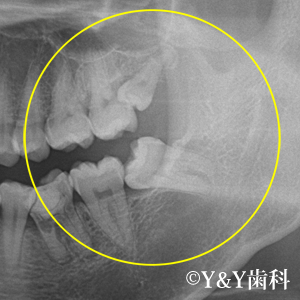

右のレントゲン写真は、横向きに生えている親知らずです。親知らずが横向きに生えていることによって、手前の歯と親知らずが密接している箇所が黒ずんでいるのを確認頂けると思います。この部分が虫歯になっています。このようなケースの親知らずは抜歯するべきです。